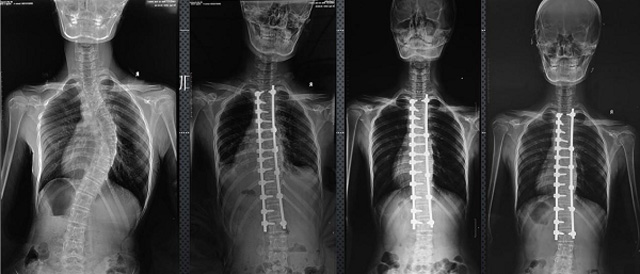

(7)全身拼接功能對(duì)有較大尺寸全脊柱拼接圖接桂成金下股分成幾次拍攝,再經(jīng)過秋件開在骨科開展的全脊柱畸形矯治工作中,雖然CT. MRI也能獲取全脊柱影像,接圖像,以便于長(zhǎng)度、角度、力線等測(cè)量和察脊柱在重力情況下但不能進(jìn)行立位檢查,無法觀全景觀察。全身拼接功能是高等級(jí)DR攝取患者立位全下的功能狀態(tài)圖像,因此采用動(dòng)態(tài)醫(yī)院特別看重的動(dòng)態(tài)DR功能之一。注:圖中Cobb脊柱正側(cè)位圖像是首選的檢查方法角度的大小是反映側(cè)彎嚴(yán)重程度的一個(gè)標(biāo)準(zhǔn)。